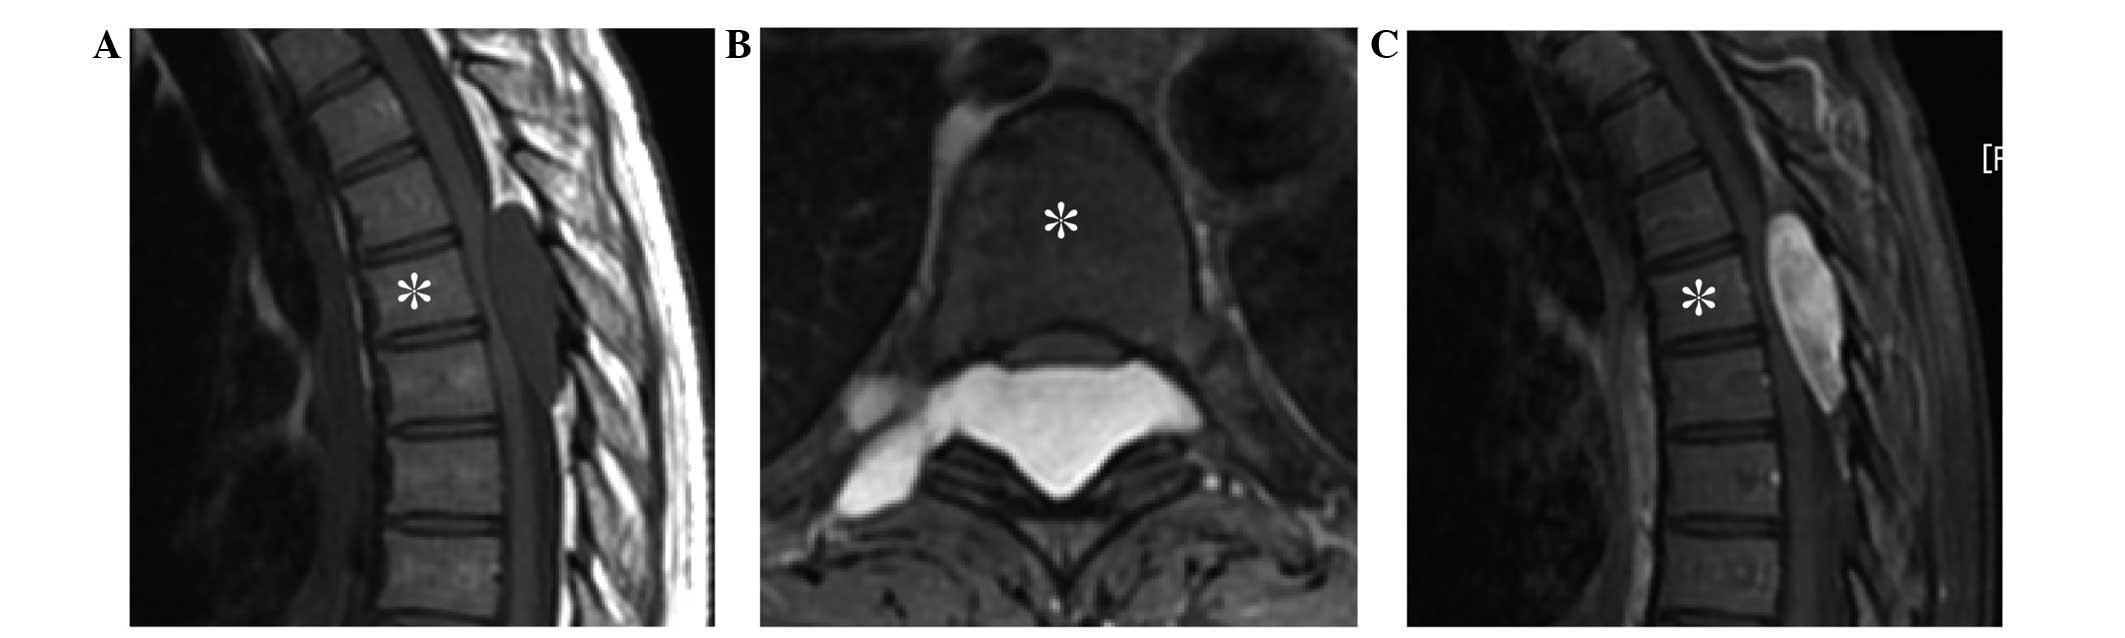

Plain radiographs and computed tomography (CT) of the spine indicated no abnormality. However, magnetic resonance imaging (MRI) revealed an epidural tumor progressing in the right foramen of the 5th and 6th thoracic vertebrae, measuring 4.6×3.7×1.4 cm, and exhibiting low intensity on T1-weighted imaging (T1-WI) (Fig. 1A), high intensity on T2-weighted imaging (T2-WI) (Fig. 1B), and diffuse enhancement on gadolinium-enhanced T1-weighted fat-suppression imaging (Fig. 1C). These findings were compatible with schwannoma. As the paralysis of the patient's lower extremities rapidly progressed and gait disturbance appeared, surgical treatment was performed. Laminectomy of the 4th, 5th and 6th thoracic vertebrae was conducted, and the whitish myxoid tumor was subsequently resected piece by piece. Following the surgery, the patient's paralysis recovered rapidly without any disturbance.

Figure 1.

Magnetic resonance imaging of the thoracic spine revealed a dumbbell-shaped, epidural tumor progressing in the right 5th thoracic vertebrae (*) foramen, exhibiting (A) low intensity on T1-weighted imaging (sagittal view), (B) high intensity on T2-weighted imaging (axial view), and (C) diffuse enhancement on gadolinium-enhanced T1-weighted fat-suppression imaging (sagittal view).